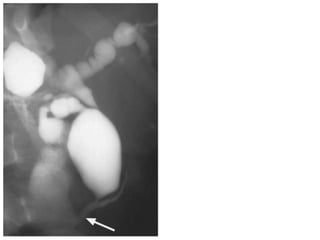

• ERCP shows a

post-cholecystectomy

stricture (arrow)

which,

characteristically,

is very short.

• ERCP showsa post-cholecystectomy stricture (arrow) which, characteristically, is very short.